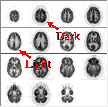

Another type of artifact is related to the placement of the patient in the scanner. To decide whether the head was tilted in the gantry, first locate the petrous ridges or bones. Normal bone has no FDG metabolism. The arrows point to the site of the petrous ridges (in plane 15 in this scan). The petrous bone appears in a PET brain scan as the absence of activity between the cerebellum and the inferior temporal lobe.

The asymmetry in activity in the plane containing the petrous ridges implies that the head was tilted in this scan. When the head has been positioned properly the absence of activity that is caused by the petrous bones should be symmetrical between the left and right sides. In this example the right petrous bone (on the left side of the image) was in the image plane to a greater degree than was the left petrous bone (on the right).